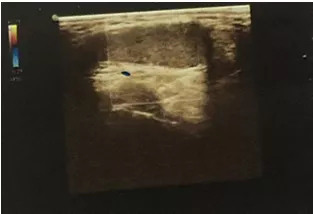

泌尿外科收治一名18歲男性青少年,反復(fù)右側(cè)睪丸疼痛2天,2天前出現(xiàn)右側(cè)睪丸疼痛稍腫脹,無(wú)其他不適,查陰囊彩超:右側(cè)睪丸、附睪較左側(cè)明顯增大,右側(cè)附睪頭實(shí)質(zhì)回聲增強(qiáng)不均,雙側(cè)睪丸、附睪血流信號(hào)未見(jiàn)明顯異常,當(dāng)時(shí)予對(duì)癥處理后疼痛好轉(zhuǎn)后回家。

近日,患者疼痛腫脹加重,再次至我院急診,行急診陰囊彩超:右側(cè)睪丸腫大回聲異常并其上方異?;芈晠^(qū),未見(jiàn)明顯血流信號(hào),未排睪丸扭曲可能,左側(cè)睪丸、附睪位置偏高,血流分布尚正常。

彩色多普勒超聲血流圖是最具有診斷價(jià)值的影像學(xué)檢查,可以詳細(xì)、實(shí)時(shí)地觀察睪丸內(nèi)的血流情況及其變化,目前被廣泛應(yīng)用于睪丸扭轉(zhuǎn)的診斷和鑒別診斷。睪丸內(nèi)動(dòng)脈血流信號(hào)明顯減少或消失是診斷本病的最可靠標(biāo)準(zhǔn)。